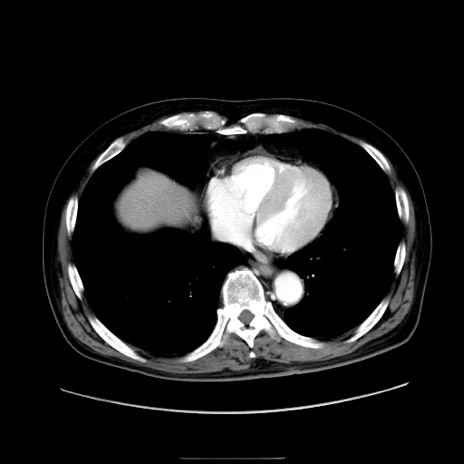

症例30(横断像)

【症例】80歳代男性

【主訴】臍周囲痛

【現病歴】約6時間前から臍下部痛が出現。次第に腹部膨隆・背部痛も生じてきたため来院。背部痛の場所は変化しない。

【身体所見】意識清明、BT 36.3℃、BP  131/87mmHg、P 87bpm、SpO2 100%(RA)、臍周囲自発痛・圧痛あり、反跳痛なし、自発痛部位に一致して板状硬あり、腹部膨隆、腸雑音減弱、CVA tenderness両側陰性。